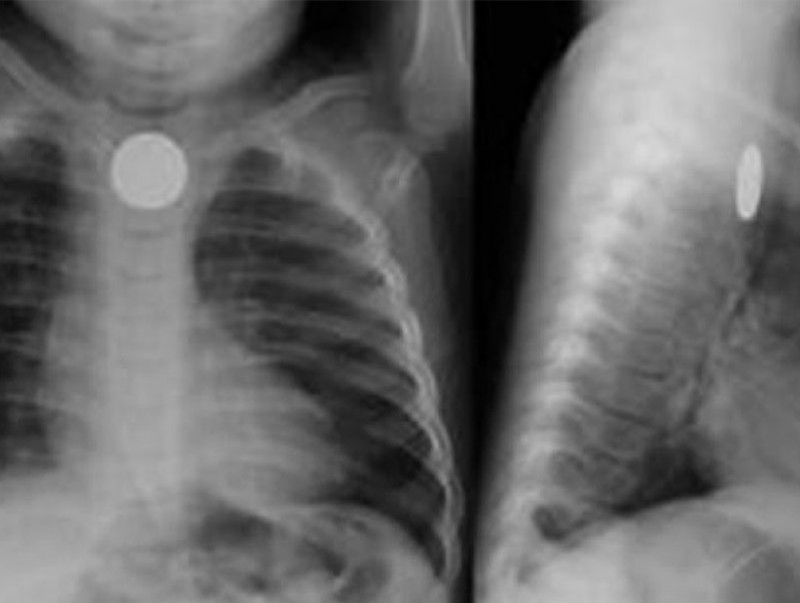

Улсын хэмжээнд бага насны хүүхдүүд товчин зай залгих тохиолдол сүүлийн жилүүдэд нэмэгдэж байна. 2024 оны эхний улирлын байдлаар товчин зай, соронз, ээмэг зэрэг гадны биет залгисан 55 тохиолдол бүртгэгдсэн байна.

Товчин зай нь алсын удирдлага, тооны машин, машины түлхүүр, тоглоом, цаг, ярианы ном, дуутай мэндчилгээ зэрэг олон төрлийн эд зүйлсэд байдаг. Товчин зай нь хүний биед ороод нэг цагийн дотор улаан хоолой, ходоодны салстыг түлэх, амь насанд аюултай тул цаг алдалгүй эмнэлгийн байгууллагад хандах хэрэгтэйг анхаарна уу.